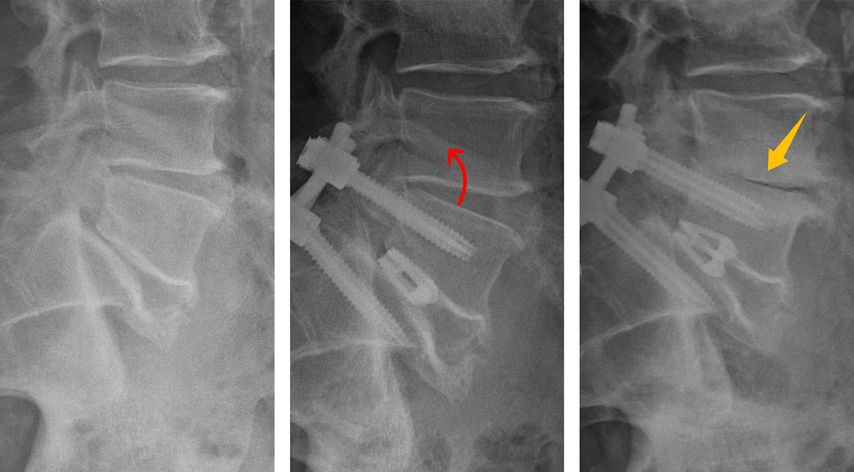

Abb. 3: Beispiel einer zunehmenden Degeneration im Segment L4/5 nach Spondylodese im Segment L5/S1: Eine multifaktorielle Ursache bei segmentaler Hypolordose im Indexsegment mit kompensatorischer Hyperlordose und Retrolisthese im kranialen Nachbarsegment, Adipositas und Nikotinabusus kann postuliert werden

In den vergangenen Jahren hat sich das Verständnis der sagittalen Wirbelsäulenparameter deutlich erweitert und dieses Wissen findet zunehmend Anwendung im klinischen Alltag. Neben klassischen Messgrößen wie der Lendenlordose oder der Beckenneigung werden zunehmend auch individuelle patientenspezifische Zielwerte herangezogen. Aber nicht nur die globale Balance der Wirbelsäule ist hier von großer Bedeutung. Auch bereits eine Deformität eines einzelnen Segmentes kann maßgeblich sein. Eine fehlende oder unzureichende Lordose im operierten Indexsegment zwingt angrenzende Segmente in pathologische Kompensationsmechanismen, um das sagittale Gleichgewicht zu erhalten. Die hierbei auftretende Hyperlordose und Retrolisthese im Nachbarsegment führt zu unphysiologischen biomechanischen Belastungen der Bandscheibe und Facettengelenke (Abb. 1). Dies kann ein Mechanismus und Treiber der „Anschlussdegeneration“ sein. Eigene Untersuchungen zeigten, dass eine konsequente Wiederherstellung der Lordose nach einer monosegmentalen Fusionsoperation das Potenzial hat, die Kompensationsmechanismen im direkt angrenzenden Segment deutlich zu reduzieren (Abb.2 ). Auf solche Erkenntnisse sind zunehmend auch Implantathersteller eingegangen und bieten neue Implantate an, die helfen sollen, die Lordose wiederherzustellen. So finden sich etwa zunehmend hyperlordotische Cages für ventrale wie auch dorsale interkorporelle Verfahren am Markt und eröffnen zusätzliche Möglichkeiten, die sagittale Balance individuell anzupassen.